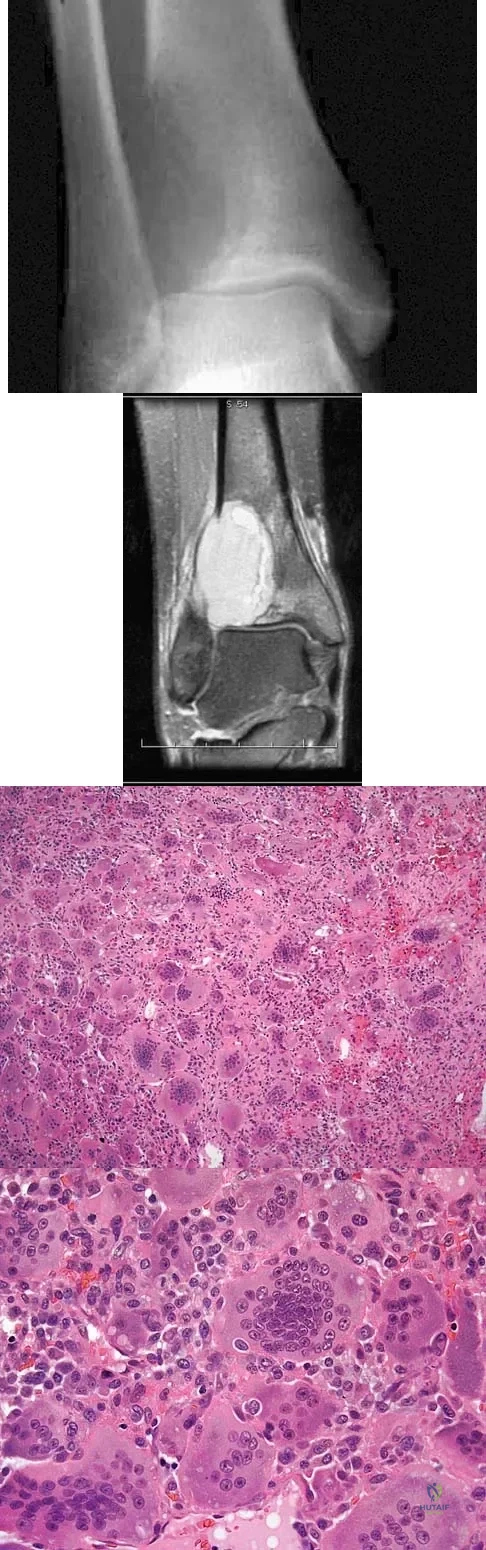

A 19-year-old girl has had pain and swelling in the right ankle for the past 4 months. She denies any history of trauma. Examination reveals a small soft-tissue mass over the anterior aspect of the ankle and slight pain with range of motion of the ankle joint. The examination is otherwise unremarkable. A radiograph and MRI scan are shown in Figures 45a and 45b, and biopsy specimens are shown in Figures 45c and 45d. What is the most likely diagnosis?

Explanation